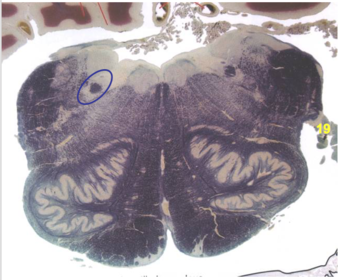

| Middle cerebellar peduncle | |

| Superior cerebellar peduncle | |

| Anterior spinocerebellar tract | |

| Principle nucleus of V | |

| Mesencephalic V tract | |

| Trigeminal root fibers | |

| Motor nucleus of V | |

| Cerebellar vermis | |

| Lateral lemniscus | |

| Medial longitudinal fasciculus | |

| Medial lemniscus | |

| Ventral trigeminothalamic tract | |

| Longitudinal pontine fibers (c-spinal, c-bulbar, c-pontine fibers) | |

| Transverse pontine fibers (dark) | |

| Pontine nuclei (pale) | |

| Central tegmental tract | |

| ALS | |